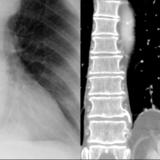

Bronch Cyst 1 CT

Date: 05/12/2004

Views: 4666